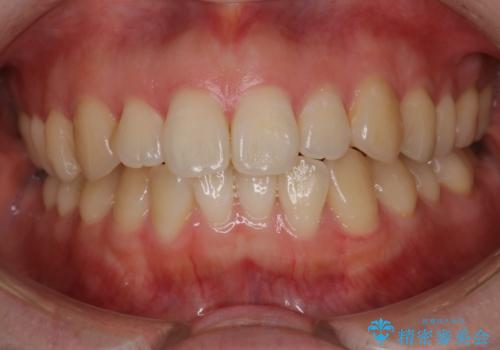

マウスピース矯正で前歯のガタツキを改善! 短期間で治療完了

過蓋咬合・上顎前突・叢生を改善するマウスピース矯正